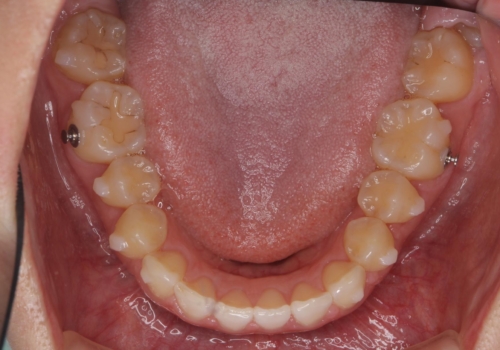

出っ歯に見える前歯の改善 部分ワイヤーとマウスピース矯正

- 出っ歯に見える前歯の改善を希望され、来院されました。

マウスピースでは改善の難しい歯の動きを部分ワイヤー矯正で整えたのち、奥歯の噛み合わせや細かい歯の並びをマウスピース矯正インビザラインで整えていきます。

最終的な前歯の並びに大変満足いただくことができました。